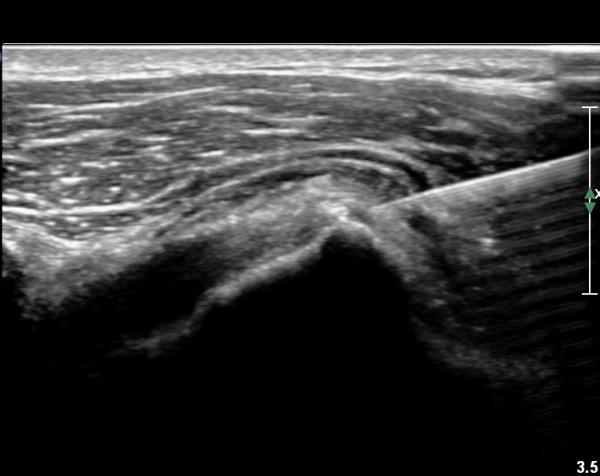

°ß°©ÇÏ±Ù°Ç ÇϺΠÁ¾´Ü¸é°Ë»ç¿Í Ⱦ´Ü¸é°Ë»ç °ß°©Çϱٰdz»  ¼®È¸È­ À½¿µÀÌ  °üÂûµÈ´Ù(»çÁø 3, 4).

°ß°©ÇÏ±Ù°Ç È¾´Ü¸é°Ë»ç»ó ¼Ò°áÀý ÇÊÁú°ñº¯È­¿Í °ß°©ÇÏ±Ù°Ç Áߺο¡ °í¿¡ÄÚ µ¢¾î¸®°¡ °üÂûµÇ°í